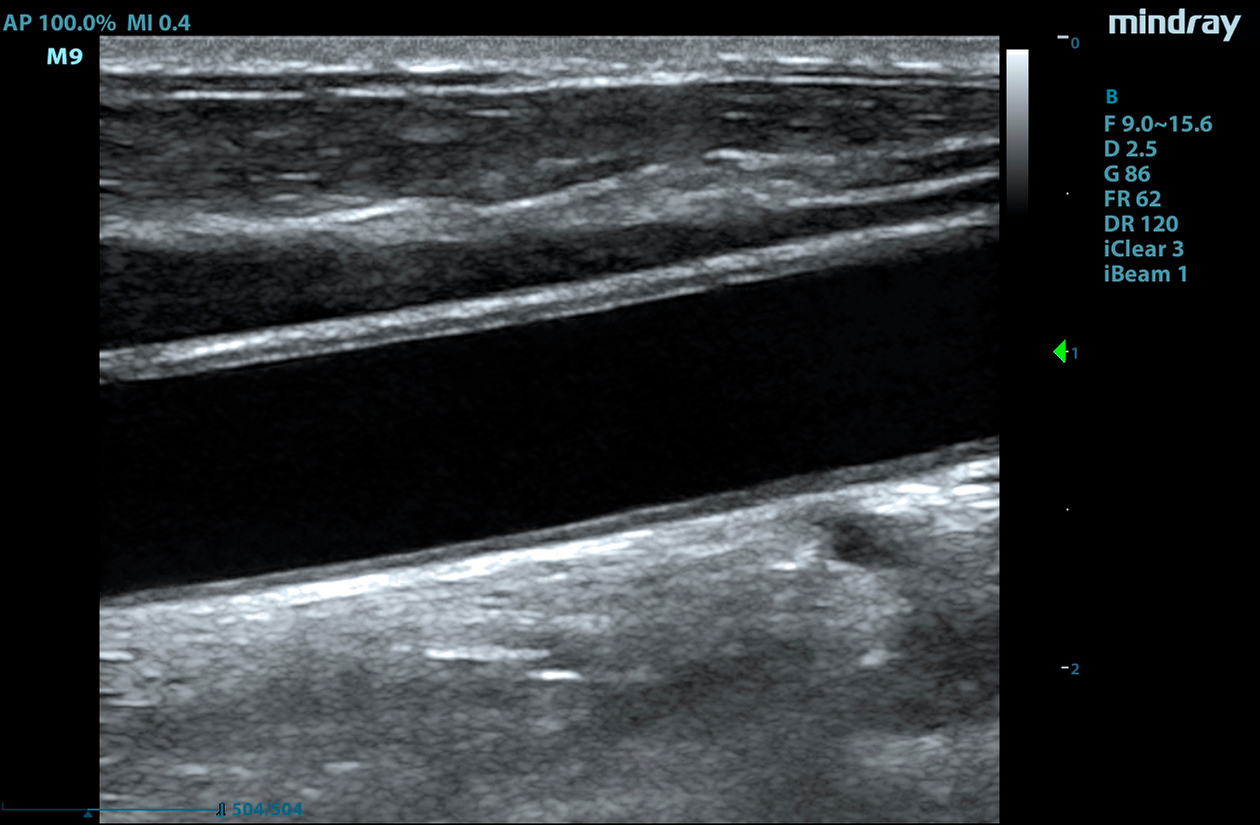

The M9 Ultrasound System Ruby Edition offers a fully-featured, compact ultrasound solution for your most challenging point-of-care exams. Delivering image clarity and advanced capabilities previously only available on larger, cart-based systems, the M9 System defines the new standard for intelligent performance in a mobile, laptop design.

Equipped with single crystal transducers and 3T™ technology for a wide range of exams, the M9 System is a versatile platform for advanced imaging in the vascular lab, emergency departments, critical care environments, and anesthesia practices. The System’s slim profile and ergonomic design allow for effortless flexibility and mobility. Whether it be ultrasound guided procedures at the patient’s bedside or transesophageal echocardiography (TEE) imaging in the critical care unit, this platform can do it all.